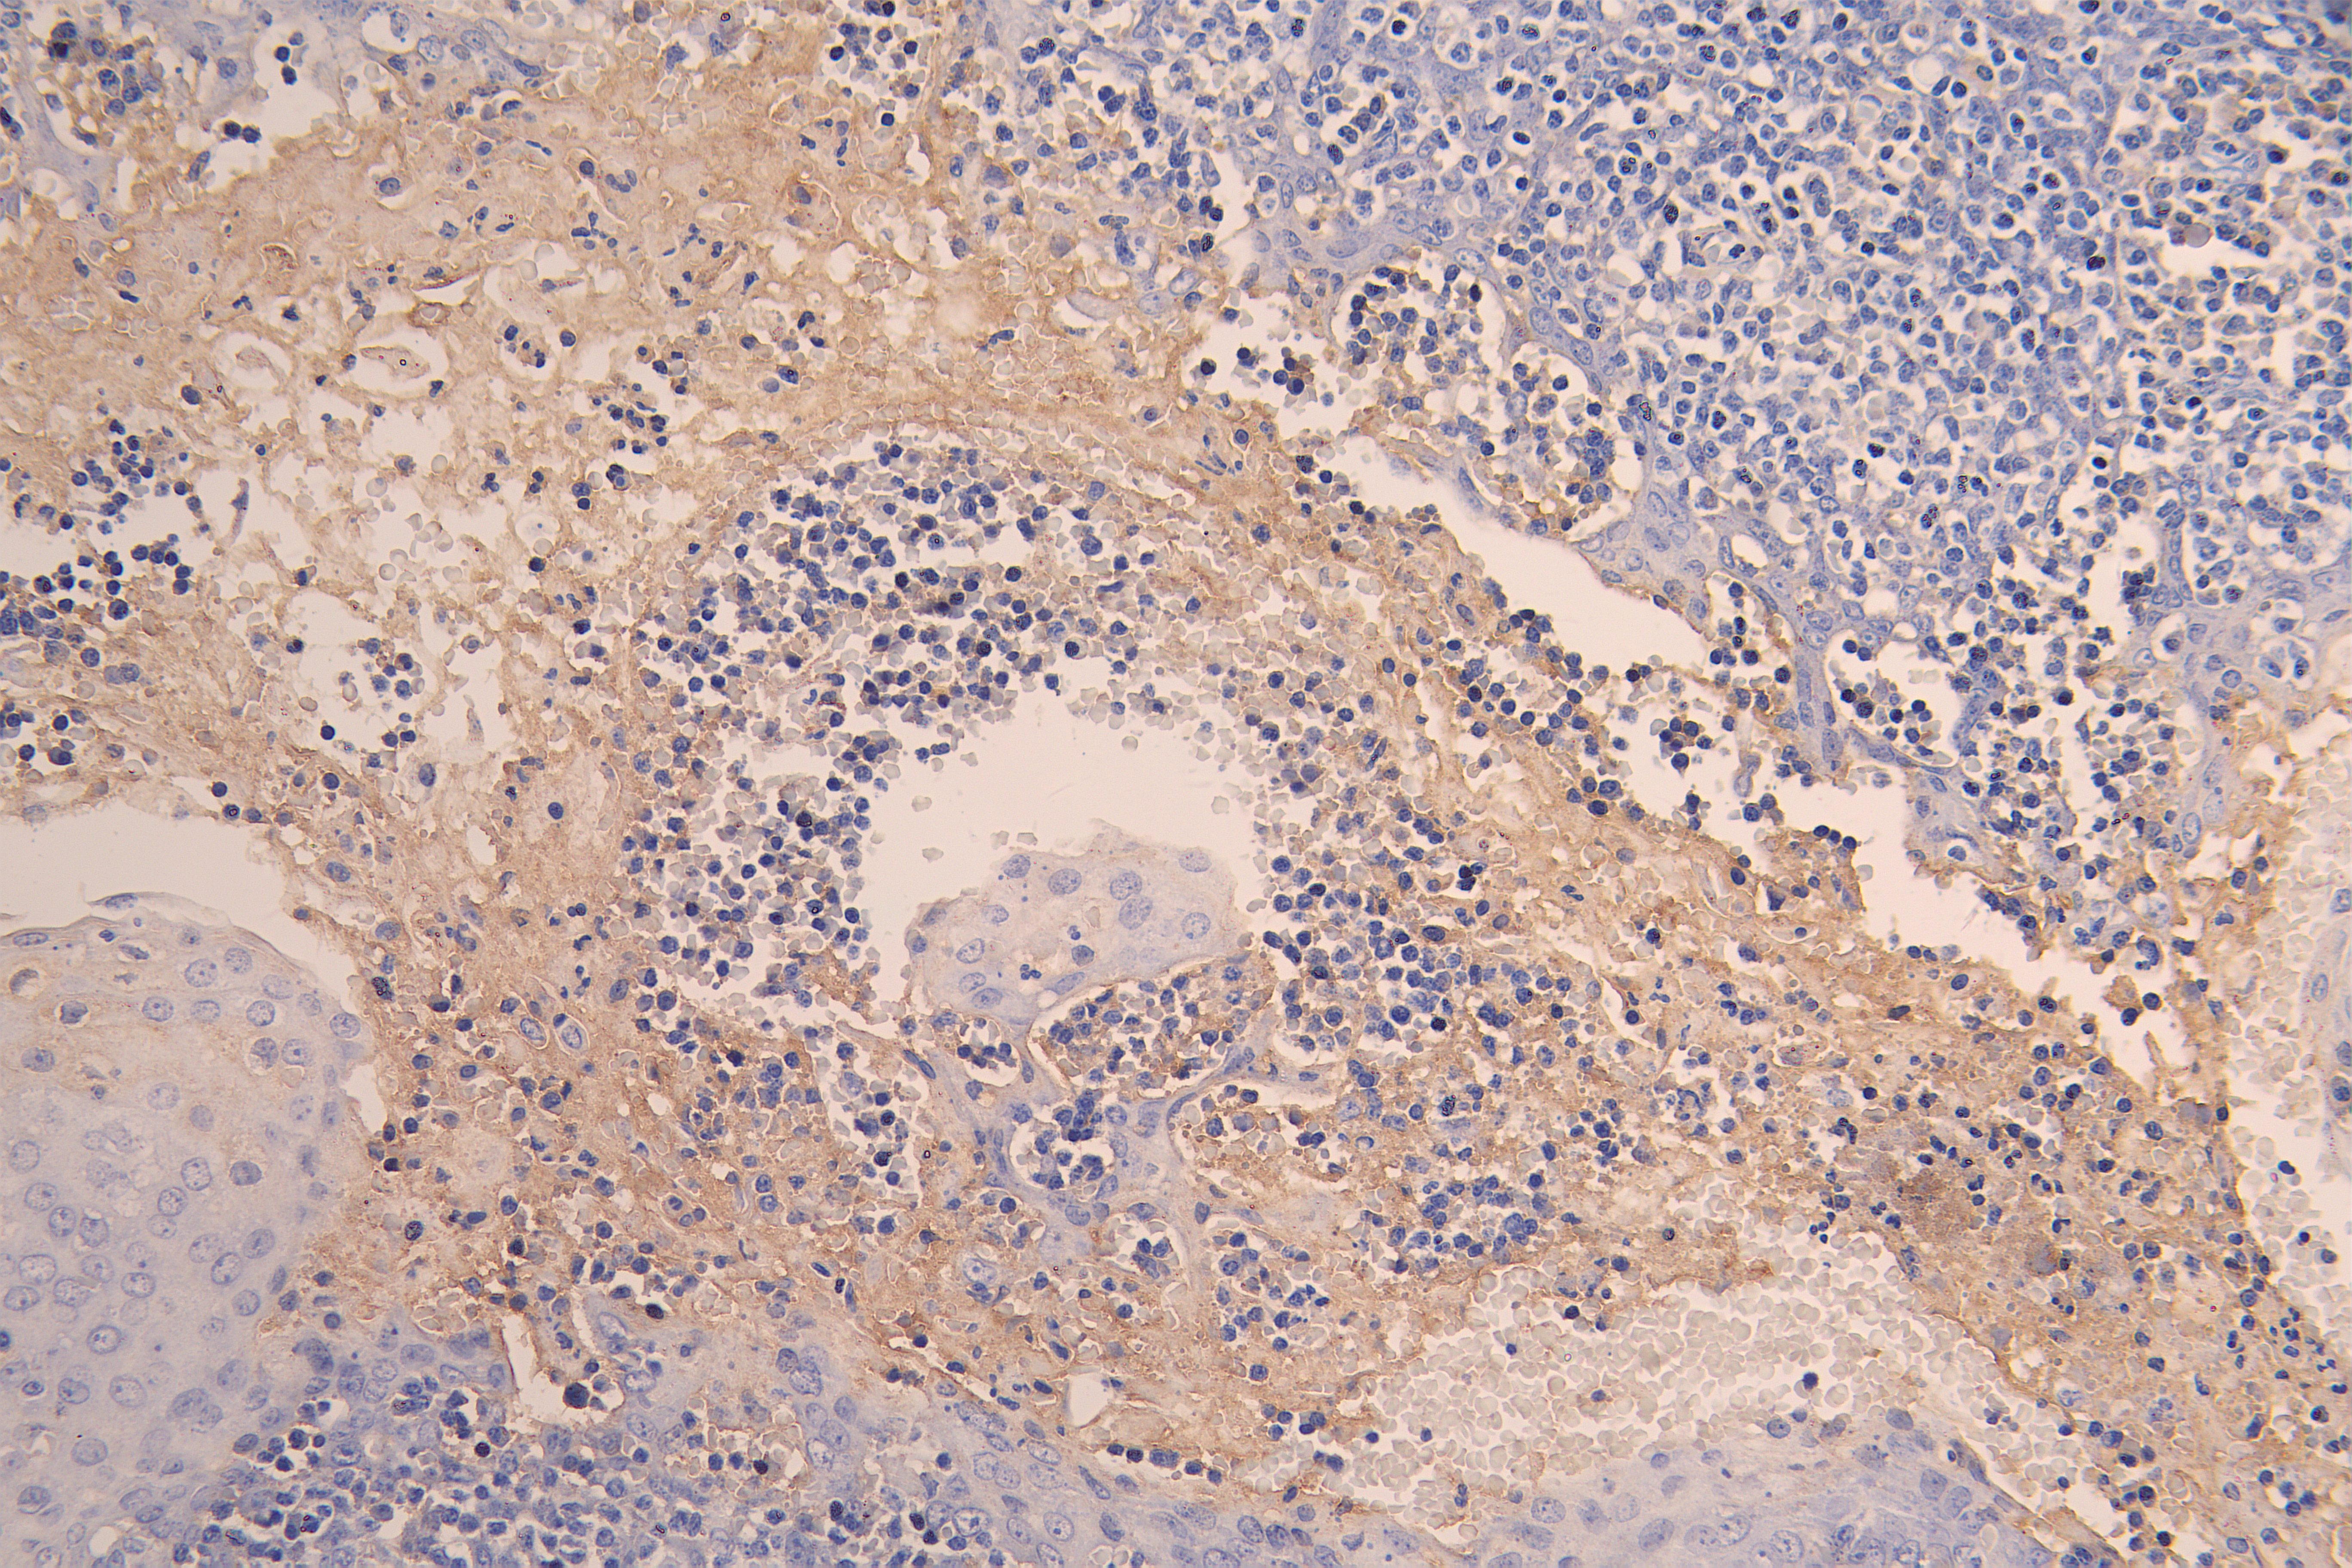

IHC image of CSB-RA004928MA1HU diluted at 1:200 and staining in paraffin-embedded human tonsil tissue performed on a Leica BondTM system. After dewaxing and hydration, antigen retrieval was mediated by high pressure in a citrate buffer (pH 6.0). Section was blocked with 10% normal goat serum 30min at RT. Then primary antibody (1% BSA) was incubated at 4°C overnight. The primary is detected by a Goat anti-human polymer IgG labeled by HRP and visualized using 0.05% DAB.